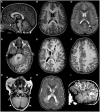

Macrocephaly affects up to 5% of the pediatric population and is defined as an abnormally large head with an occipitofrontal circumference (OFC) >2 standard deviations (SD) above the mean for a given age and sex. Taking into account that about 2-3% of the healthy population has an OFC between 2 and 3 SD, macrocephaly is considered as "clinically relevant" when OFC is above 3 SD. This implies the urgent need for a diagnostic workflow to use in the clinical setting to dissect the several causes of increased OFC, from the benign form of familial macrocephaly and the Benign enlargement of subarachnoid spaces (BESS) to many pathological conditions, including genetic disorders. Moreover, macrocephaly should be differentiated by megalencephaly (MEG), which refers exclusively to brain overgrowth, exceeding twice the SD (3SD-"clinically relevant" megalencephaly). While macrocephaly can be isolated and benign or may be the first indication of an underlying congenital, genetic, or acquired disorder, megalencephaly is most likely due to a genetic cause. Apart from the head size evaluation, a detailed family and personal history, neuroimaging, and a careful clinical evaluation are crucial to reach the correct diagnosis. In this review, we seek to underline the clinical aspects of macrocephaly and megalencephaly, emphasizing the main differential diagnosis with a major focus on common genetic disorders. We thus provide a clinico-radiological algorithm to guide pediatricians in the assessment of children with macrocephaly.